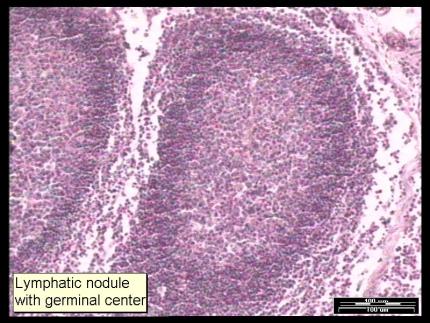

Ganglio Linfático con centro germinal (100 micrómetros)

A nivel de la corteza tiene una zona redondada llamada seno o centro germinal, rica en linfocitos B. Formado por nódulos o folículos linfoides, esto se llamaría EL PARENQUIMA,que es la sustancia del ganglio y es la parte secretoria. imágenes 4,6,7,8.